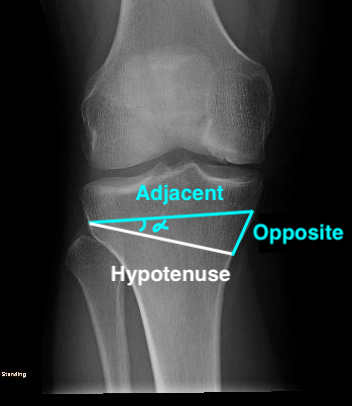

B. Trigonometry Calculation

Tangent angle formula

Tan Angle = opposite/adjacent

Opposite = adjacent x Tan angle